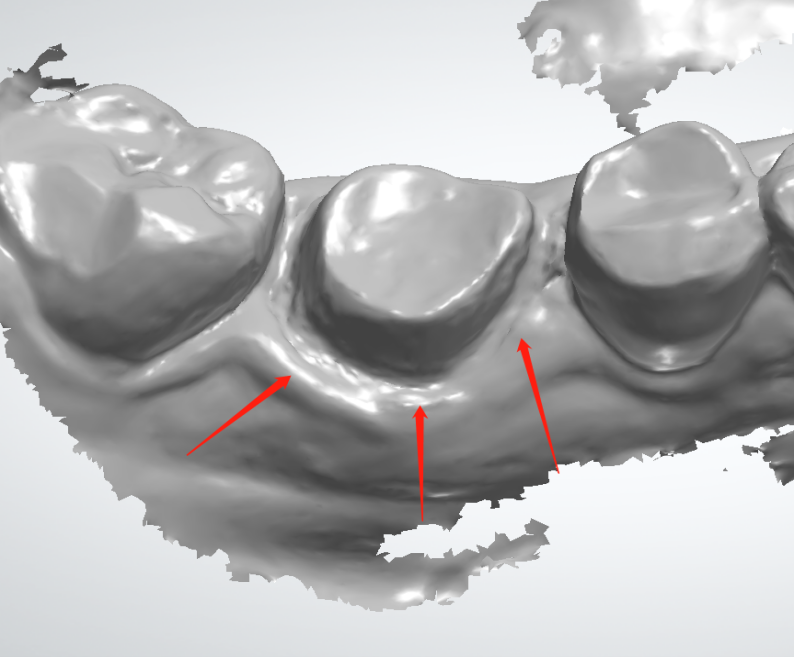

We can see the margin is much better in pic1 than what we see from pic2. And there is a little spot of the margin covered by the gum tissue. The margin is blur while the scanning is switched to pain color view.